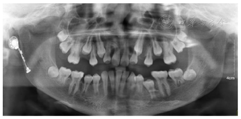

根尖片示:11自根中向远中弯曲约35°,属Ⅱ类弯曲牙,牙根发育至Nolla9期,21牙根发育至Nolla9期,腭侧见两颗正置锥形多生牙;12、22牙根发育至Nolla9期。

CBCT示:上颌恒牙胚萌出间隙不足,根据Moyers混合牙列分析法,牙弓现有长度为177.4 mm,牙弓应用长度为181.6 mm,拥挤度为4.2 mm。42缺失;11、21、22发育至Nolla9期;55、16、65、46冠部低密度影及牙本质中层,根管内未见高密度充填影,根尖周未见明显异常。53、63牙根吸收不足1/3,13、23发育至Nolla8期。

头颅侧位片示:下颌相对颅底位置靠前,趋向Ⅲ类错

,上下切牙舌腭向倾斜,骨龄CS1起始期。

患者母亲身高矮小、智力正常,下颌前突,曲面体层片示上下颌共缺失5颗恒牙(14、24、32、34、44),18、28、38、45、48阻生。

2020年10月11日门诊局麻下摘除下颌双侧前磨牙区多生牙及其牙囊3颗。

2020年12月21日口腔颌面部CBCT精确定位、笑气镇静+4%肾上腺素-盐酸阿替卡因注射液局部浸润麻醉下先行拔出恒中切牙腭侧多生牙,同期切除部分牙龈暴露双侧上中切牙牙冠最宽径。4个月后11仍未有萌出迹象,21萌出,与31反

余牙评估恒牙发育阶段,于Nolla8期时拔除乳牙,减轻继承恒牙萌出阻力。治疗过程中逐步拔除上下颌双侧第一、第二乳磨牙及右上乳尖牙。根据恒牙萌出情况逐步磨除

治疗结果:总疗程共19个月,矫治后患者上颌双侧中切牙基本牵引至正常位置,左上恒中切牙及左下恒中切牙反

解除,上前牙恢复正常突度及倾斜度,下前牙恢复正常突度,稍舌倾。上下颌切牙覆

覆盖正常。上颌双侧恒尖牙未萌,间隙保留,左上恒尖牙异位好转,牙冠近中向倾斜程度减轻。下颌缺失右侧恒侧切牙,间隙关闭并排列整齐。通过慢速扩弓与及时拔除萌出通道上相应乳牙及多生牙,上下颌前磨牙、磨牙自然萌出到正常位置并建

。埋伏多生牙拔除手术顺利,无术后感染及复发。所有萌出恒牙完成窝沟封闭术。

随访:矫治治疗结束后随访期5个月,疗效稳定,发现左下第二恒前磨牙根尖舌侧出现一多生牙牙胚,由于下颌牙列无间隙,考虑该多生牙无保留价值,且有导致35牙根吸收的风险,建议患者择期拔除。